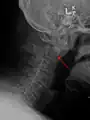

Type 2 dens fracture